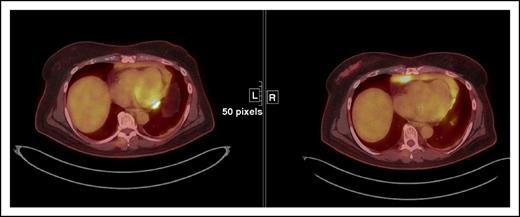

This case illustrates a discrepancy between the revised Lugano Classification (PD) and the immune-related response criteria (PR) given the fact that the immune-related response criteria do not take into consideration PET/CT findings. This type of discrepancy is particularly notable in cases with bone marrow involvement. Oftentimes, lymphomatous involvement of the bone marrow is either not measurable (due to absence of soft tissue component) or imperceptible on CT. Therefore, these findings cannot be integrated in the tumor burden of the immune-related response criteria. Restaging PET-CT is at 12 weeks. Restaging PET/CT 2 at 20 weeks demonstrates new areas of FDG uptake in the left side of T9 vertebral body (arrows) and increasing uptake in the left acetabulum, suggesting increasing extent of marrow disease, whereas this is barely seen on CT. Marked physiologic uptake is also seen in brown fat (asterisks).